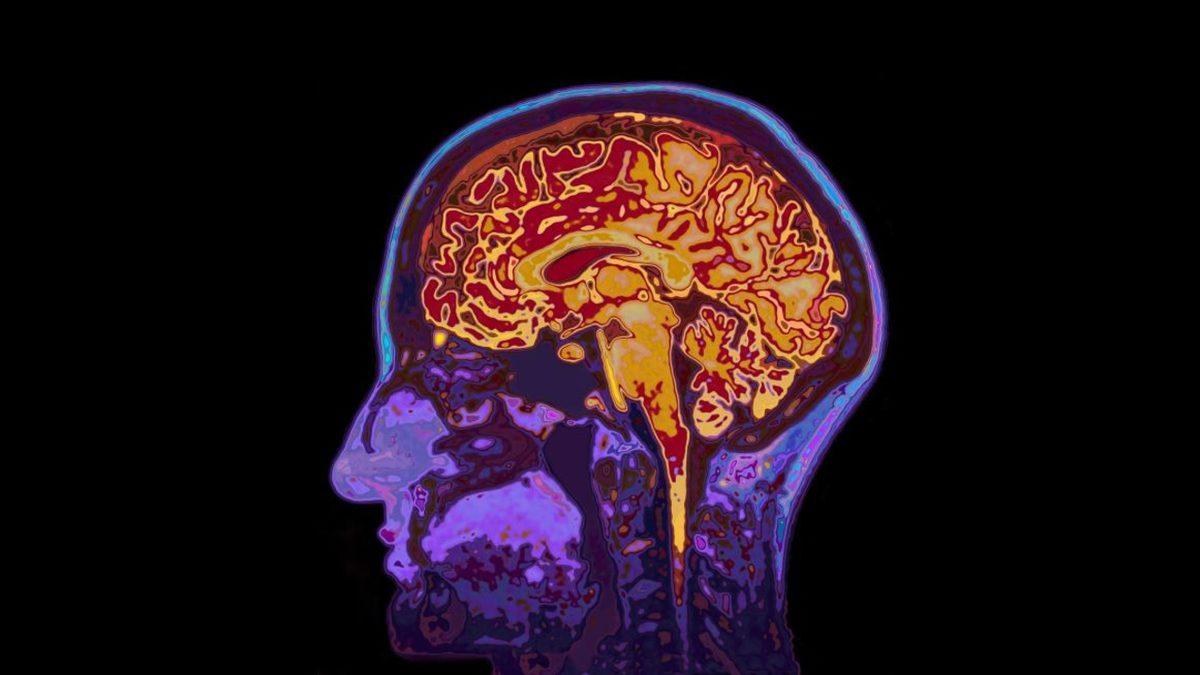

En başında belirtmeliyiz ki hayır, dejà vu bir hastalık ya da hastalık belirtisi değildir. Epilepsi hastalarında bazen nöbetler eşliğinde yaşansa da, hiçbir sağlık sıkıntısı olmayan insanlarda da olabilen dejà vu; beynin işleyişindeki küçük bir anomaliden kaynaklanmaktadır ve söz konusu hissin zaman zaman ortaya çıkması fiziksel ya da ruhsal bir sorununuz olduğu anlamına gelmez. Fakat bu hissiyat düzenli olarak tekrarlanıyorsa bir anormallik olabilir ve acilen bir doktora muayene olmak gerekir.

Yetişkin bireylerde stres, yorgunluk ve benzeri nedenlerden kaynaklanabilen dejà vu, daha ziyade 'epilepsi' hastalarında görülüyor. Nöbet öncesinde, bilinç açıkken ortaya çıkan dejà vu, kişinin daha şiddetli ataklar geçirmesine sebep olabiliyor. Bu nedenle, bilhassa çocukluk ve ergenlik dönemlerinde dejà vu çok sık yaşanıyorsa mutlaka bir doktora başvurulmalı ve epilepsi hastalığı olup olmadığı anlaşılmalıdır.

Bir diğer açıklamaya göre ise beynin sağ lobu ile sol lobu milisaniyeden daha ufak bir zaman farkıyla çalışır ve bunun sonucunda da bir olayı bir taraf daha önce algıladığı için, daha geç algılayan taraf bu olayı daha önce yaşamış gibi olur. Yani başka bir deyişle bu olay, sinir aksonlarındaki küçük bir sapmadan kaynaklanır.

Yapılan araştırmalarda elde edilen bulgulara göre, temporal lob krizleri gelmeden hemen önce dejà vu yaşanabilmektedir. Söz konusu yakınlık, nörolojik düzeyde anomoli oluşturacak elektrik akımlarının deja vuya sebep olduğu neticesini güçlendirmektedir. Ayrıca, dejà vunun Alzheimer hastalığının erken tanısında yararlı olabileceği fikri de öne sürülmektedir. Ancak bu teori şu an için doğruluk kazanmamıştır.

Beyinde meydana gelen minör devre arızaları

Bir diğer teoriye göre de beyniniz ‘hata verdiğinde’ bu, epileptik nöbete benzer bir elektriksel arızaya sebep olur ve bu da dejà vuya yol açar.

Başka bir şekilde anlatmak gerekirse; beyninizin şu anı ve geçmişi kontrol eden kısımları aynı anda çalıştığında beyin hata verir ve dejà vu olursunuz.

Böyle durumlarda beyniniz şimdi olan bir olayı bir ‘anı’ olarak algılar ve o anı daha önce yaşamışsınız hissine kapılırsınız. Bu tarz bir beyin hatası, düzenli olarak tekrarlanmadığı sürece herhangi bir tehlike teşkil etmez.